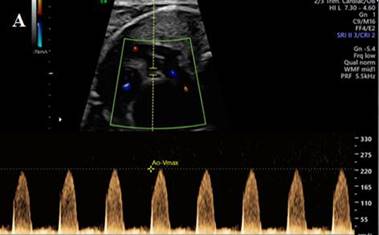

A los 3 meses del procedimiento híbrido se

procede a la remoción del cerclaje percutáneo (Figura 2A y 2B) y oclusión del stent ductal (Figura 2C).

Fig. 2. Angiografía. Dilatación de ambos cerclajes

de ramas pulmonares (A y B). Oclusión percutánea de stent

ductal (C).